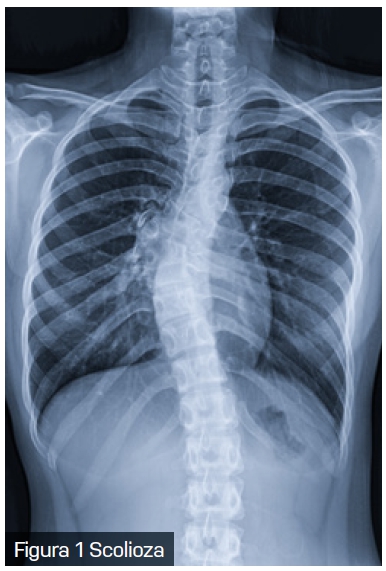

Scolioza, o deformare tridimensională a coloanei vertebrale, este o afecțiune care nu afectează doar aspectul fizic al pacientului, ci poate avea implicații semnificative și asupra sănătății respiratorii. Scolioza are o prevalență variabilă între 0,3% și 15,3% în populația generală.

Modificările structurale cauzate de scolioză au un impact direct asupra mecanicii respiratorii. Deformarea coloanei vertebrale și a toracelui reduce complianța peretelui toracic, limitează mobilitatea coastelor și afectează forța musculaturii intercostale. Aceste schimbări conduc la o scădere a volumului pulmonar și determină compresia focală a căilor respiratorii. În special la copiii cu scolioză cu debut precoce, limitarea creșterii normale a toracelui și a plămânilor poate avea consecințe pe termen lung asupra dezvoltării respiratorii.

În practica clinică, pacienții cu scolioză pot dezvolta un tipar de respirație rapidă și superficială, în încercarea de a compensa rigiditatea peretelui toracic. Această adaptare conduce la o scădere a capacității de efort și la apariția dispneei de efort, una dintre primele manifestări clinice ale scoliozei. Implicarea coloanei toracice (singură sau în combinație cu segmentul lombar) în scolioză este responsabilă pentru complicațiile respiratorii și cardiovasculare, iar distorsiunea cutiei toracice crește efortul respirator necesar.

Deși scolioza nu afectează direct mușchii respiratori, aceasta poate restricționa funcționarea lor. De exemplu, mușchii intercostali pot deveni „supraîntinși” sau pot avea dificultăți în a se extinde din cauza modificărilor dintre spațiile intercostale, ceea ce le reduce eficiența, inclusiv capacitatea de expansiune a toracelui. Deformarea cutiei toracice determină un perete toracic (și, implicit, un sistem respirator) mult mai puțin elastic, ceea ce crește efortul necesar pentru respirație.

Datorită interconexiunilor complexe dintre coloana vertebrală, stern și coaste, mișcarea și rotația vertebrelor în cazul scoliozei au un impact semnificativ asupra formei toracelui, generând o latură convexă și una concavă. Pe lângă severitatea curbei coloanei vertebrale, vârsta pacientului joacă un rol în distribuția inegală a gazelor alveolare. Reducerea capacității de a efectua efort fizic la copiii cu scolioză nu se datorează doar scăderii capacității respiratorii, ci și diminuării abilității inimii de a se adapta la cerințele metabolice crescute. De asemenea, micșorarea diametrului anteroposterior al toracelui la acești copii determină o deplasare a inimii, afectând astfel funcționarea acesteia.